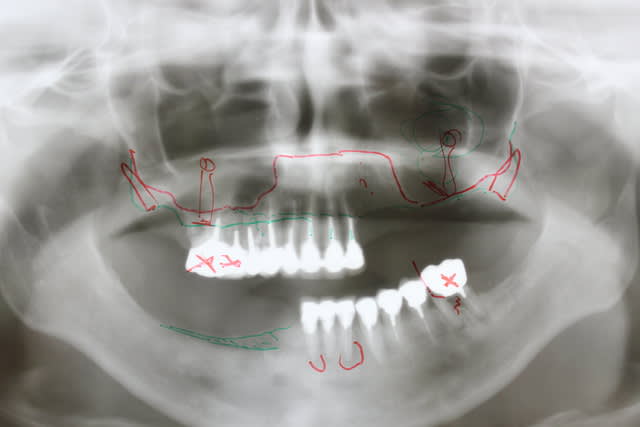

Juste pour vous dire à tous que je vis toujours

Un gros rail d os et tout posé à main levée

Ds 6 mois on fait le maxillaire

Oui et ce cas ci arrive ds qques semaines le tps de faire deux séances d ostéotension au moins

Celui ci sera plus difficile car ici pas de rail d os existant

Ton patient va mourir d'une overdose de titane ;-)

Sérieusement, je m’interroge sur la validité bio-mécanique de placer 13 implants à la mandibule, et de tout relier cela d'un bloc.

Je crois que 8 implants soient amplement suffisants : meilleur espacement entre les implants pour l'entretient et la maintenance paro